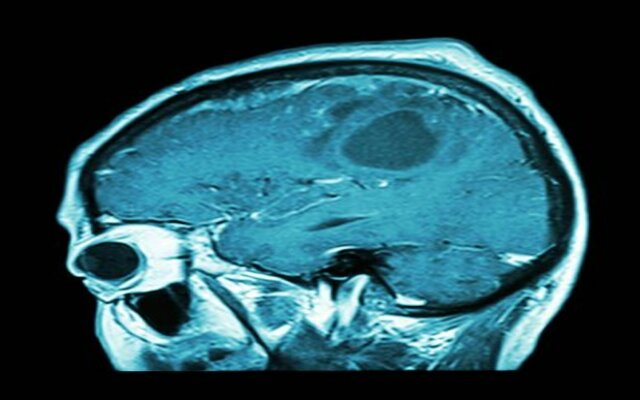

El cáncer en el cerebro es uno de los más agresivos. Sin embargo, una vacuna que ya está desarrollada puede ser el fin de esta enfermedad.

Sin embargo, los investigadores descubrieron que no todos los tumores son exactamente iguales y tampoco, todos responden bien al tratamiento con inmunoterapia. Por eso, se ha trabajado en una «inmunoterapia de precisión» para tratar a pacientes que sufren glioblastoma.

El glioblastoma es uno de los cánceres con peor pronóstico. Por eso, los pacientes que lo sufrían en el momento del estudio necesitaron una vacuna personalizada para que los resultados fueran favorables. Pero ¿cómo se hace esto?